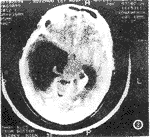

CT扫描所见 两侧脑室颞角及枕角扩大,右额角及三脑室稍受压,中线结构略左移,扩大脑室周边见低密度水肿区。右侧脑室三角区及左枕角分别见约18mm×12mm×15mm,28mm×18mm×15mm稍高密度灶,CT值53~58HU(图1)。增强扫描病灶明显均匀强化,CT值81~87HU,脑室周边无强化(图2)。CT诊断:双侧脑室占位伴梗阻性脑积水。转外院CT临床诊断同上。建议手术治疗。